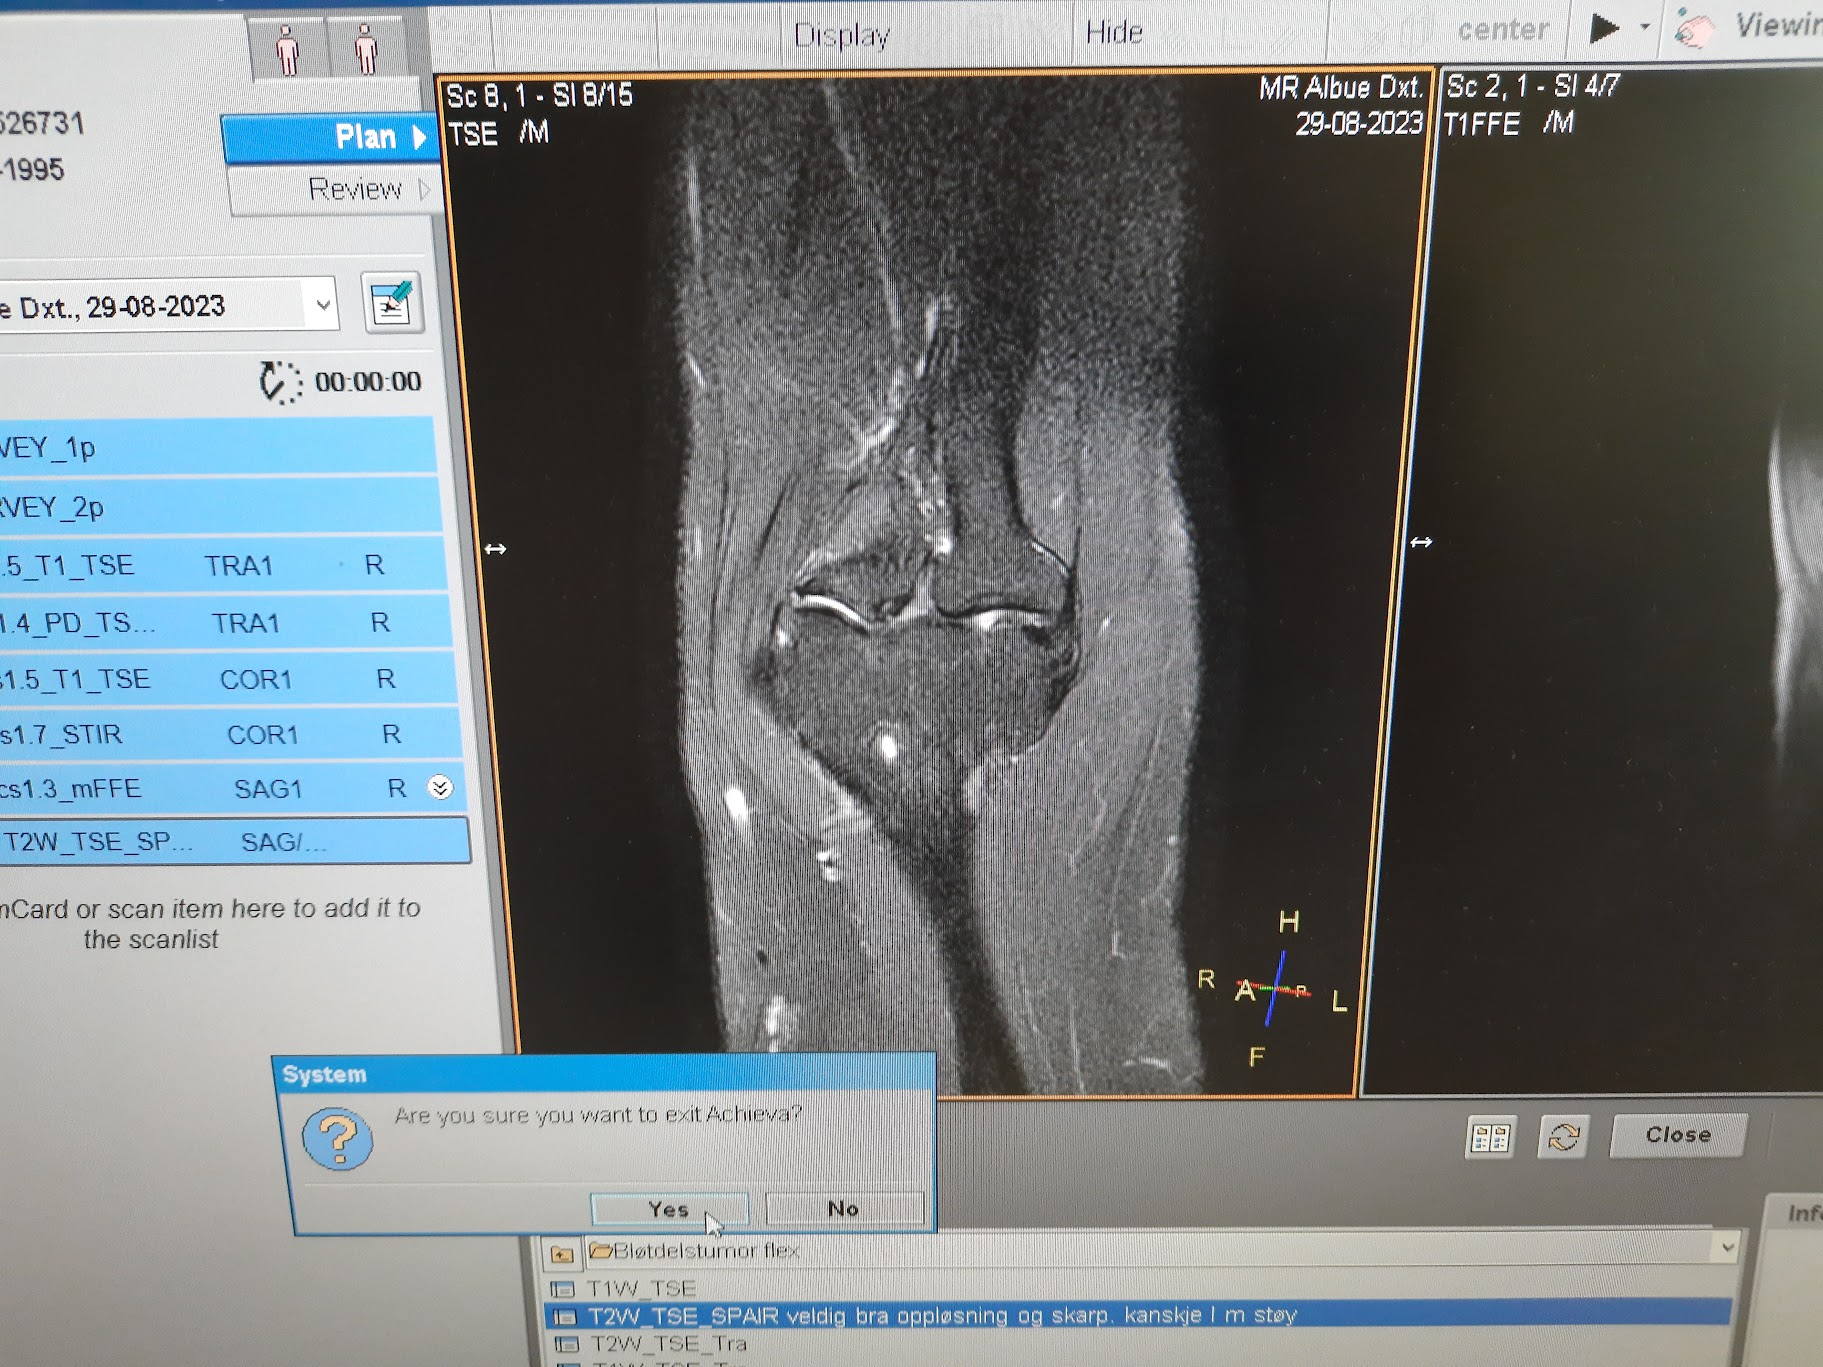

425 крон за 15 минут разговора с врачем. Норм.

Но это необходимая, хоть и не гарантированная мера для ускорения процесса получения разрешения для операции. А то ждать 2 года минимум меня не радует.

Не прошло и года, и теперь у меня есть направление к ортопеду. Ух бля, живем.

Надо бы, да. Ибо если не выйдет с учебой, другой вариант остаться - это работка. Заслужить свое место под солнцем. Я понял, что в Норвегии нет смысла бояться дно работки, платят достаточно, чтобы жить, а не выживать. Главное остаться. Ну или хотя бы денег подзаработать, чтобы было на что жить первое время как пидорнут домой.

Надо чинить, ибо работа требующая физического труда мне не по силам, а для беженцев только такие варианты и существуют.